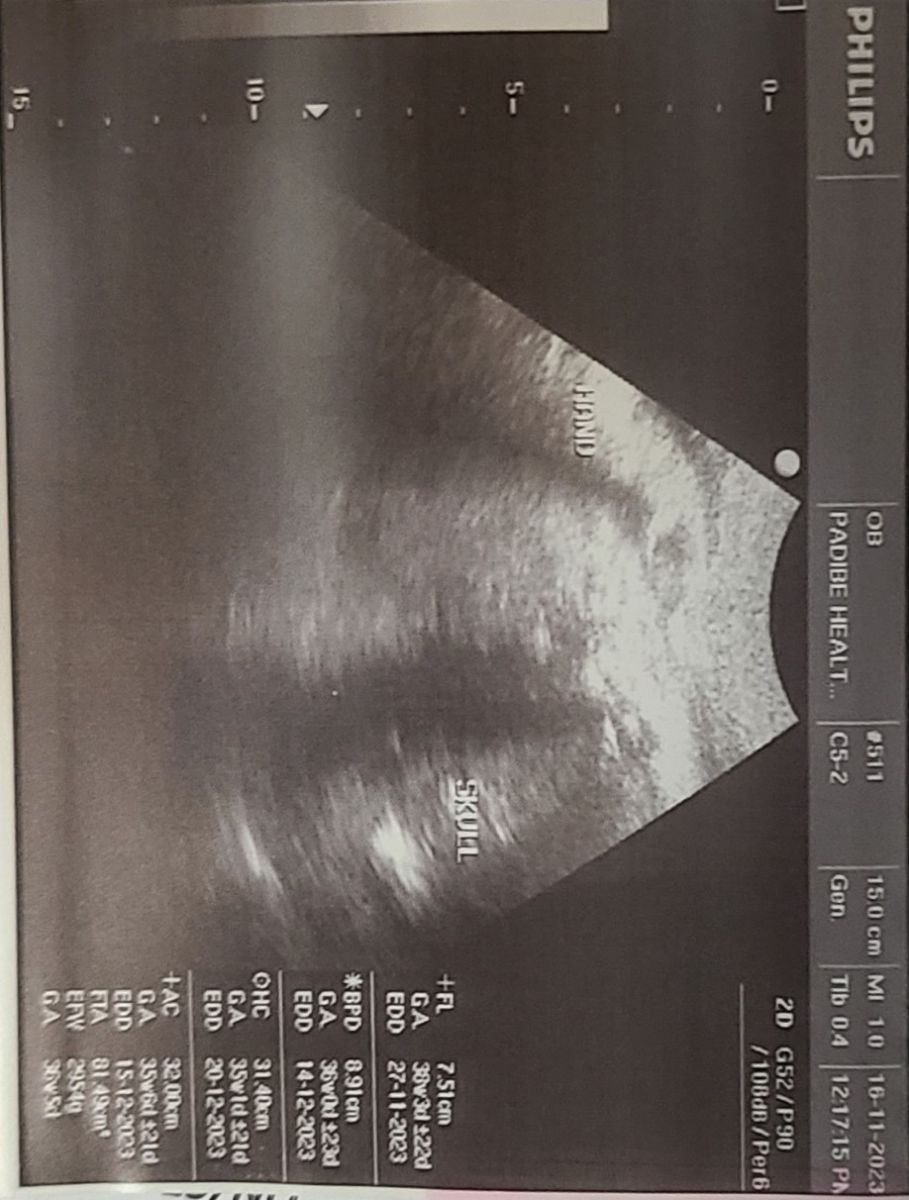

An obstetric scan done revealed a single live fetus at 36 weeks and 5 days of gestation, estimated weight of 2954 grams, mild polyhydramnios, compound presentation, (Figure 1).

Figure 1: Ultrasound scan image

At this point, the admission diagnosis was latent labour with preterm pre-labor rupture of membranes, compound presentation with hand prolapse, and severe malaria with mild thrombocytopenia.